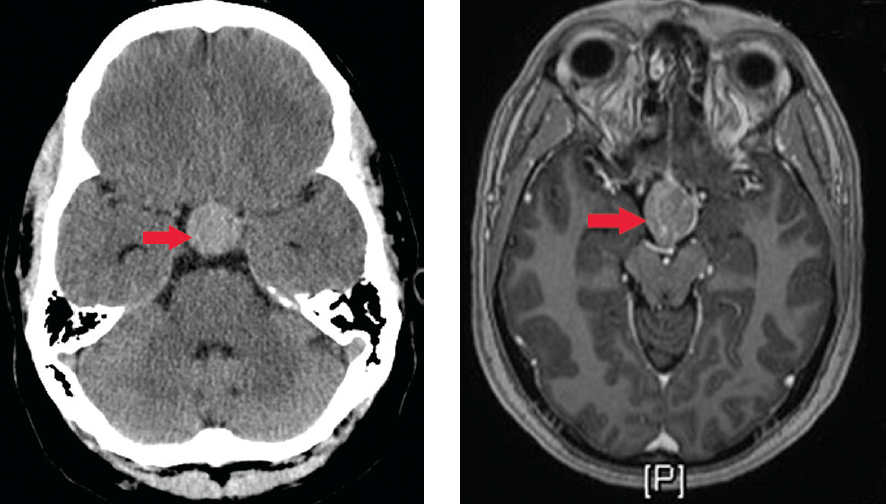

A 16 Year Old Boy Who Presented With Headache And Blurred Vision Axial Download Scientific Diagram